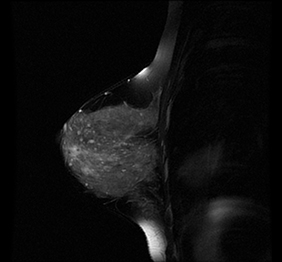

RMN San

Investigatie noninvaziva, folosita pentru a depista cancerul de san si alte anomalii la nivelul sanului.